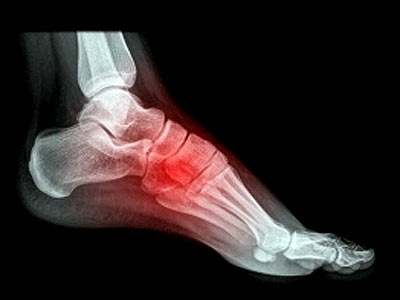

TS.BSCKII Đặng Xuân Tin cho biết gout có biểu hiện chủ yếu ở khớp và thận. Các tinh thể này khu trú ở các khớp làm chúng bị viêm tấy, đau, lâu dần gây biến dạng, cứng khớp. Khi bị gout sẽ thấy đau nhức các khớp xương, nhất là khớp ngón chân cái, sau đó có cảm giác ngứa và tróc vẩy vùng khớp khi cơn đau giảm đi, xuất hiện các cục (hạt) urat nổi dưới da, di động ở dưới vành tai, túi mỏm khuỷu, xương bánh chè hoặc gần gân gót.

Gout thường bị nhầm lẫn với các bệnh về khớp như viêm khớp dạng thấp, thoái hóa khớp, gây khó khăn trong quá trình điều trị. |

Bệnh gout có thể gây biến chứng nếu điều trị không đúng, không liên tục. Bệnh có thể hủy hoại khớp và đầu xương, gây tàn phế. Mặt khác, các hạt tophi bị loét vỡ, khiến vi khuẩn xâm nhập vào trong khớp gây viêm khớp nhiễm khuẩn, nhiễm trùng huyết. Bên cạnh đó, muối urat lắng đọng ở thận làm tổn thương thận, dẫn đến sỏi thận, suy thận, tăng huyết áp... |